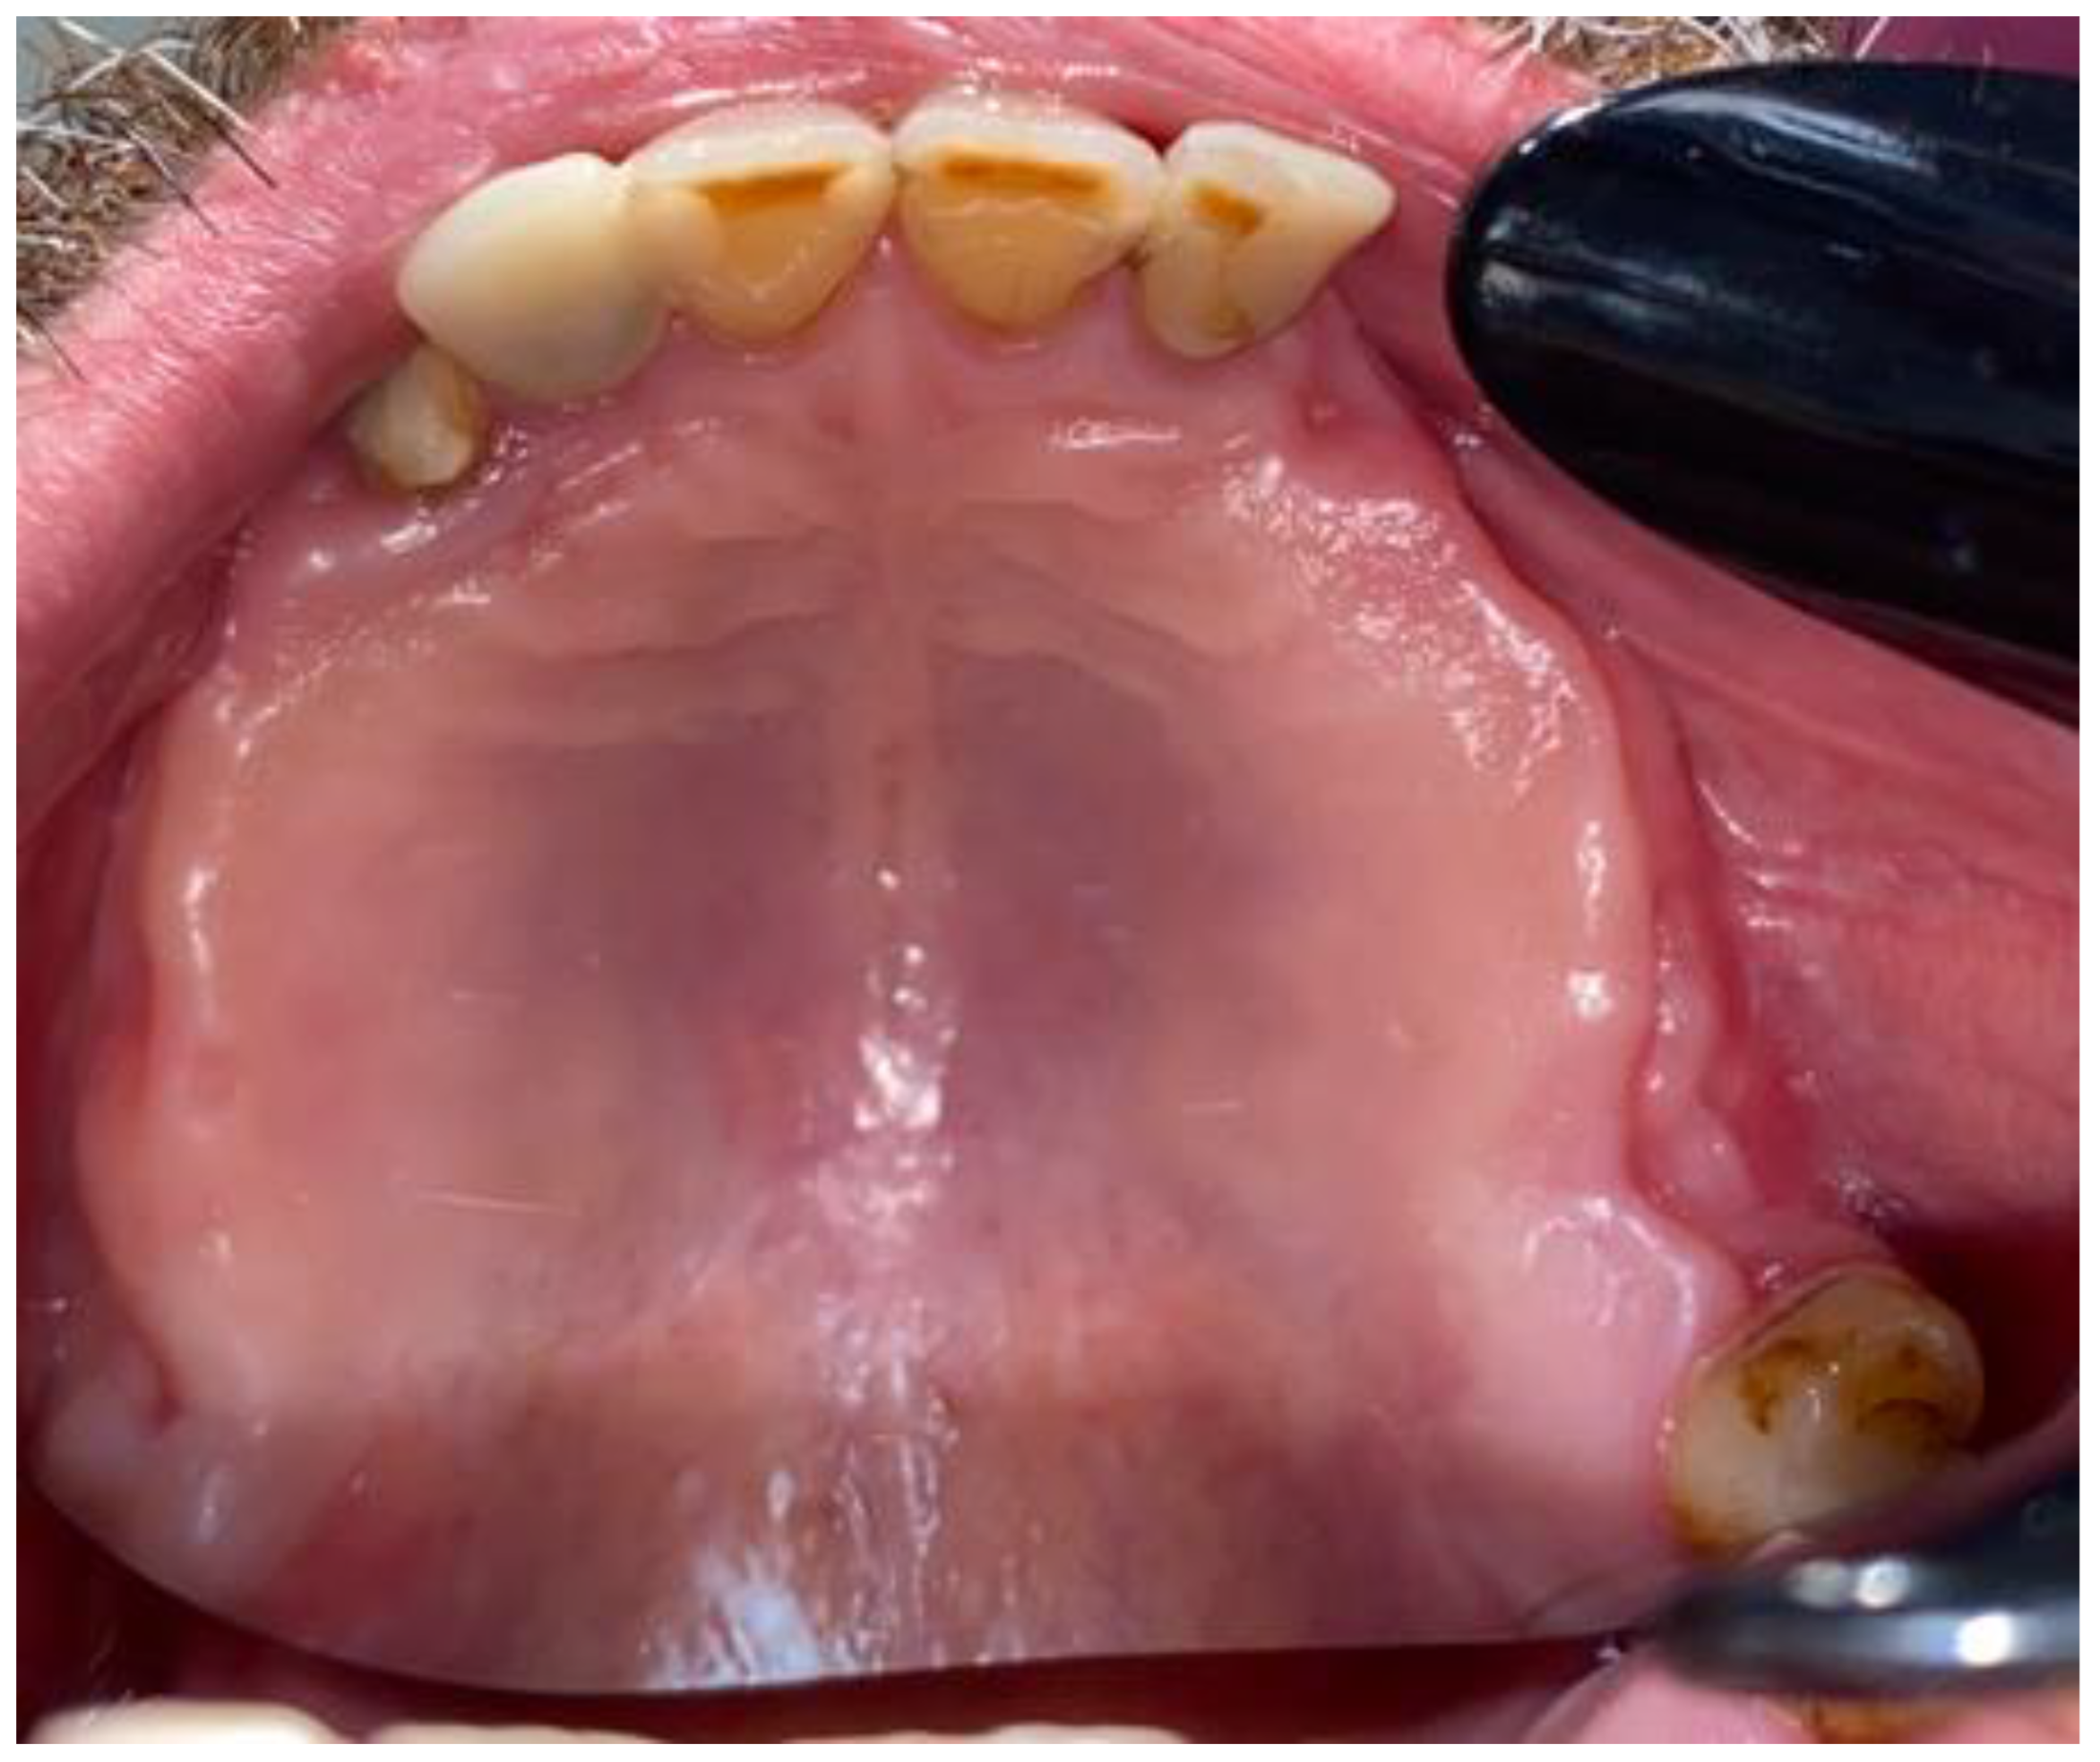

2. Case Description